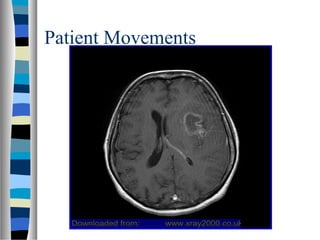

MRI artifacts

Patient Movements

Artifact